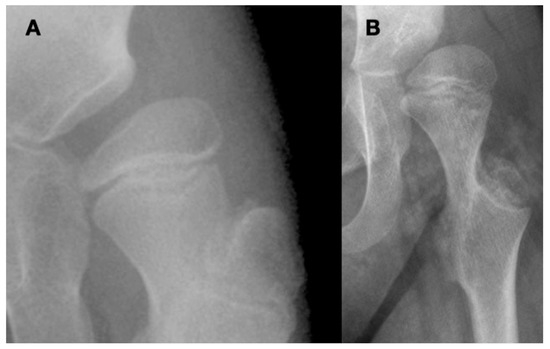

3.3.3. Pathology of Hip Development in Children with Low Tone and Muscle Weakness

3.4. Femoral Factors Influencing Hip Pathology